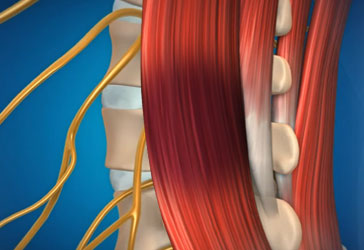

자생 비수술 보존치료를 받은 환자들을 대상으로 치료 기간을 조사한 결과 통증이 극심한 중증디스크 환자도 2개월 내에 통증이 급격히 감소하는 것으로 나타났습니다. 단, 통증이 줄었다는 것은 염증이 줄었다는 의미일 뿐 손상된 근육과 인대, 뼈와 신경 등이 회복되기까지는 최소 3개월 이상의 시간이 필요하기 때문에 디스크의 진행 단계, 척추의 퇴행 정도, 환자 개개인의 상태에 따라 치료 기간이 다릅니다. 자생은 최단 기간 안에 통증을 감소 시켜 일상 생활이 가능하도록 한 뒤 재발 방지를 목표로 지속적인 치료를 권장합니다.